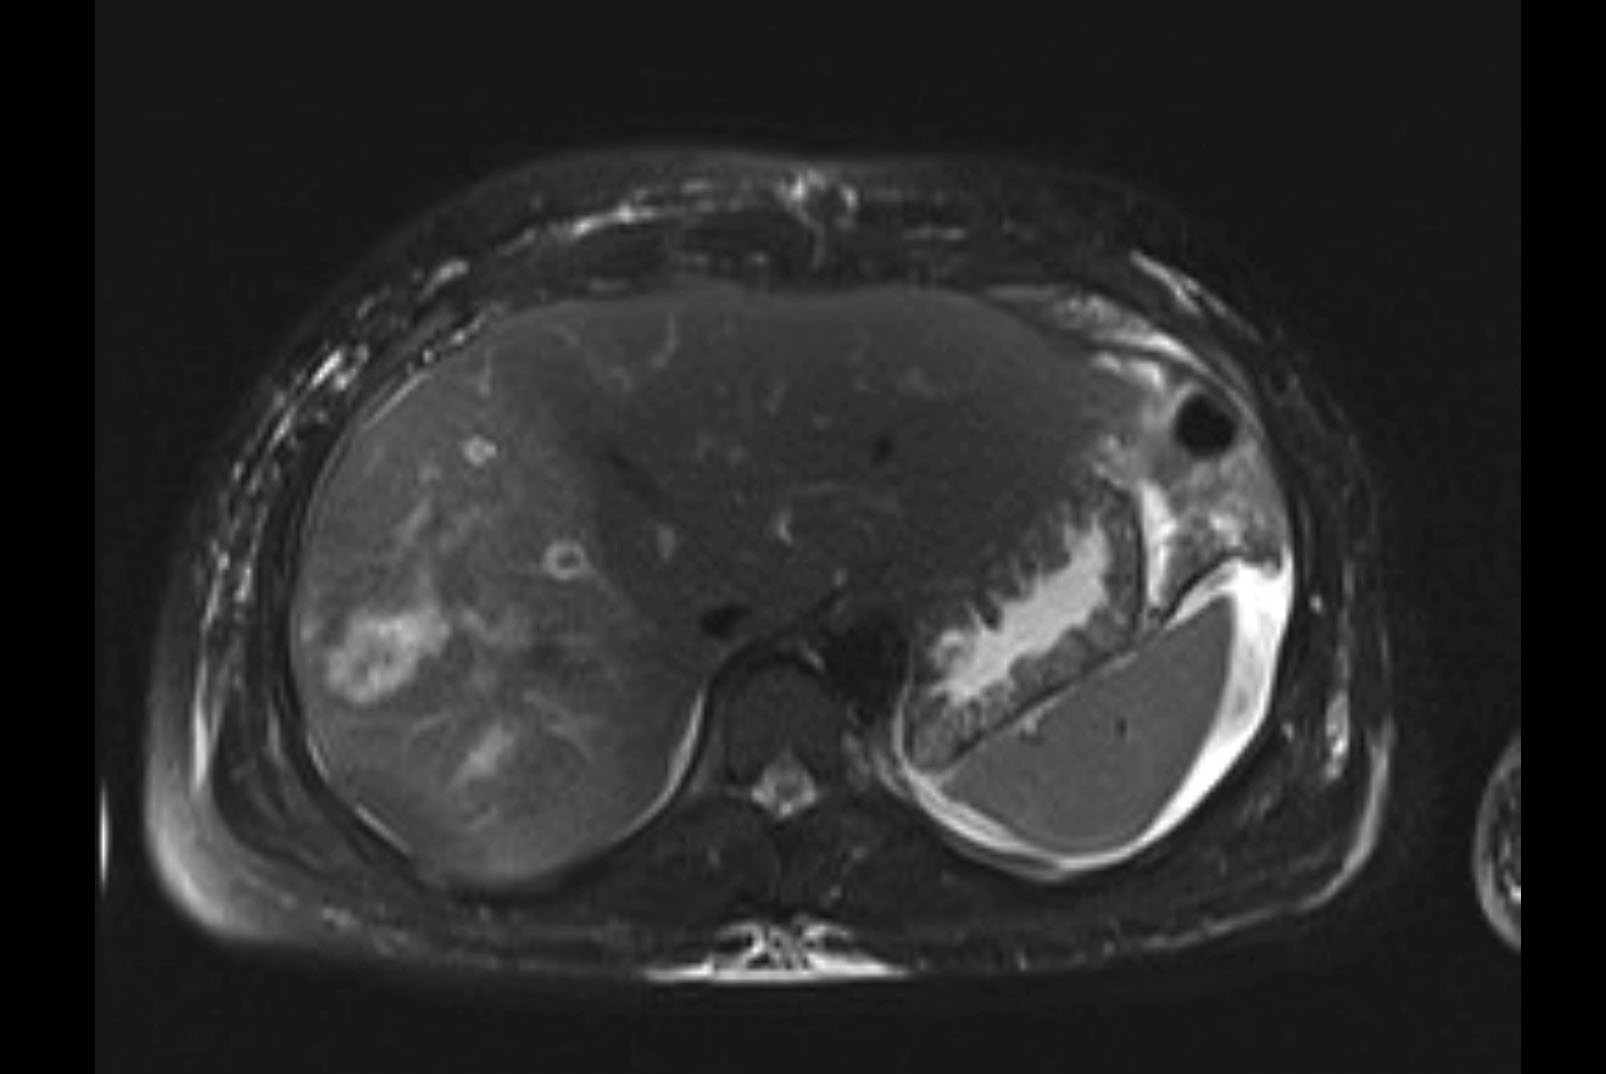

MRI T1

MRI T2